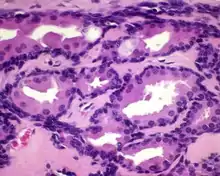

All of the tumors are unencapsulated, but are usually well defined or circumscribed. The overlying surface epithelium is not involved. The tumor shows a dual or biphasic appearance, with glandular or cystic spaces showing inner luminal secretory cells with abundant granular, eosinophilic cytoplasm subtended by basal, myoepithelial cells at the periphery, adjacent to the basement membrane. The luminal cells will often have decapitation (apocrine) secretions and will also have yellow-brown, ceroid, lipofuscin-like (cerumen) pigment granules. There is no pleomorphic, limited mitoses, and no necrosis.[2]

Immunohistochemistry can be performed to confirm the biphasic nature of the tumor. All cells are positive with pancytokeratin and epithelial membrane antigen; only the luminal cells are positive with CK7; only the basal cells are positive with CK5/6, p63, S100 protein. CD117 can be positive in either population. The cells are negative with chromogranin, synaptophysin and CK20.[2]